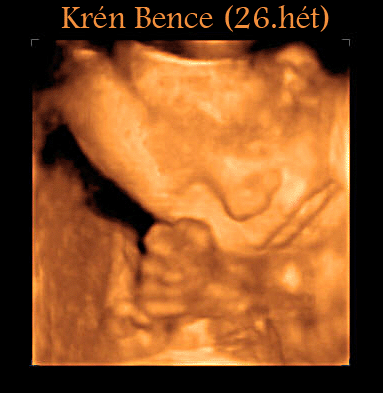

26 hetesen2007.12.13 20:04